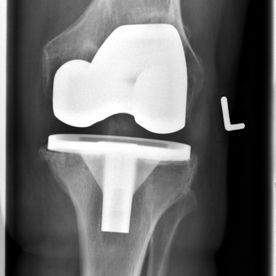

Bei einem entsprechenden Eingriff werden von den gelenkbildenden Knochenoberflächen, nachdem dort spezielle Schnittblöcke aufgebracht worden sind, lediglich wenige Millimeter dicke Knochenscheiben entfernt und anschließend auf die so vorbereitete Oberfläche eine Oberflächenersatzprothese (aus Metall) einzementiert.

Sind sowohl die Innen- als auch die Außenseite des Gelenkes fortgeschritten verschlissen, wird eine so genannte wie „bicondyläre“ Oberflächenersatzprothese eingesetzt (= komplette Knieprothese). Sollte der Verschleiß nur die Innenseite des Kniegelenkes betreffen, ist die Versorgung mit einer Schlittenprothese möglich.

Totalendoprothese

Monoschlittenprothese